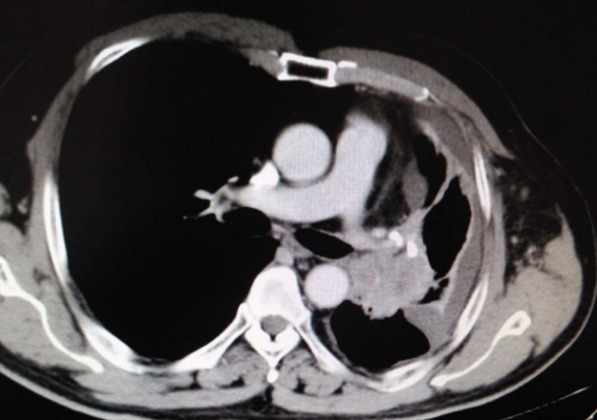

到了医院后,医生给刘先生进行简单的查体,并开了血尿常规和肺部CT的检查,检查结果提示刘先生的肺部出现了大问题。医生:“CT显示两肺之间有很多病灶,肺部淋巴结有肿大的迹象,尤其是左上叶的肺部这个病灶,不排除是肿瘤,我建议你再查一个电子支气管镜来明确病因。”刘先生:“肿瘤?是癌症吗?”医生:“这个不好说,需要看检查结果才能定下来。”刘先生在医生的要求下进行了电子支气管镜的检查。晴天霹雳,检查结果显示肿瘤确诊为肺癌晚期刘先生的检查结果出来后,找到医生进行复诊,医生对着刘先生不禁叹气。医生:“结果不是很理想,基本可以确诊为肺癌。”

刘先生:“医生,我这是早期还是晚期?还能治好吗?”医生:“病理报告显示是晚期肺癌,我建议你最好赶紧住院治疗。”医生根据刘先生的情况写下如下病例内容(部分):患者体温36.7℃、血压128/85、身高179cm、体重72kg。肺部CT提示肺部淋巴结肿大,左上叶肺部存在肿瘤,电子支气管镜提示支气管黏膜慢性炎症伴鳞状上皮化生以及局限性癌变。左肺上叶刷片提示存在癌细胞,病理活检显示肺癌晚期。主诉:剧烈咳嗽、咳中带血、胸闷气短、全身乏力。病史:患者具有长期吸烟史,工作环境位于粉尘较多地段并且不配备防尘面具。近日因感冒引发咳嗽加剧,自行服用感冒药治愈感冒后发现咳嗽并未缓解,再次服用咳嗽药物无果,咳中带血后前往医院就诊,目前均已停药。